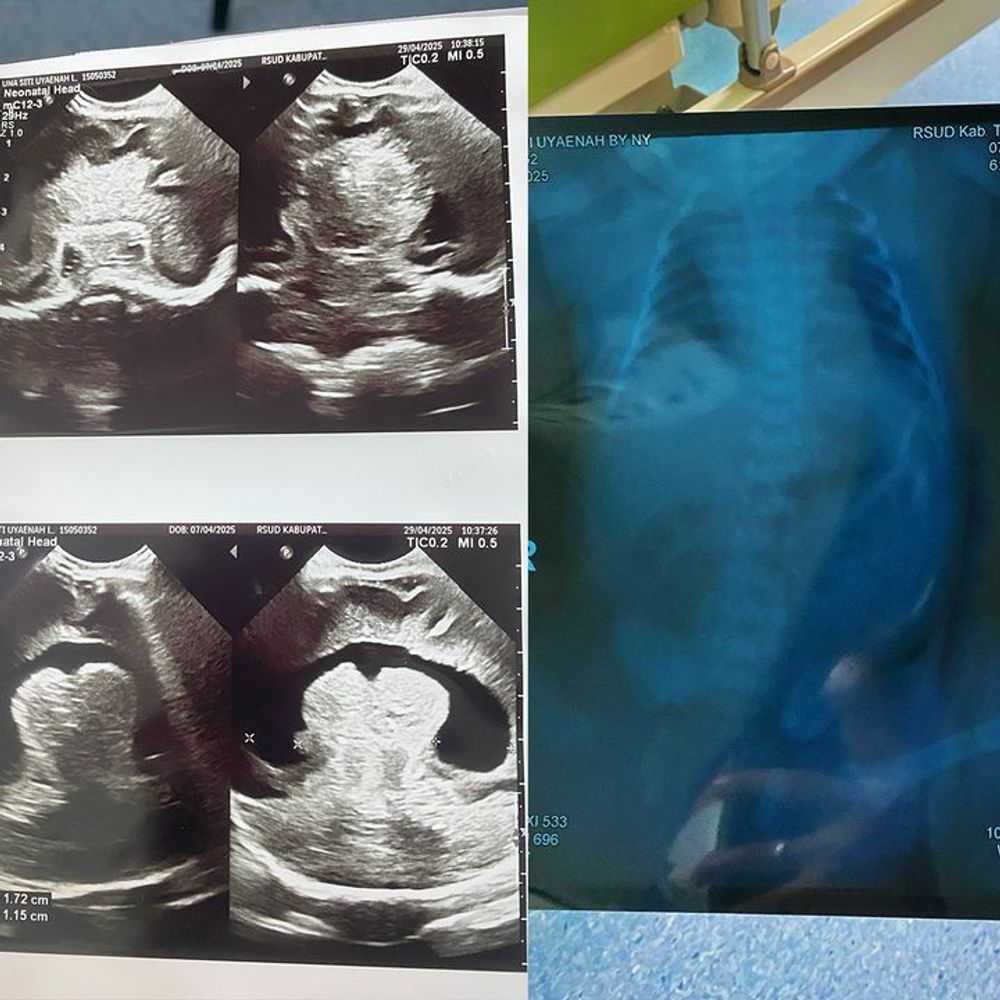

Since she was only 6 months old, Navisha has never truly known good health. She was diagnosed with hospital-acquired pneumonia, where the air sacs in her lungs (alveoli) are filled with fluid or pus instead of air. Since then, hospitals have become her second home, with constant admissions she could never avoid.

Things grew worse when Navisha turned 4. She was hospitalized again and referred to a hospital in Jakarta, where doctors diagnosed her with Nephrotic Syndrome. This kidney disorder causes waste and toxins to build up in her blood, leaving her body swollen and requiring repeated blood transfusions.

Today, Navisha is still under intensive care. Doctors say her condition remains unstable and must be closely monitored. Beyond hospital treatment, Navisha also needs special milk and medication that are not covered by government insurance.